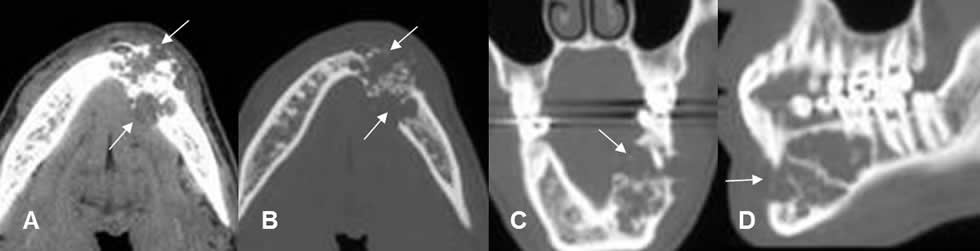

Fig 58. Quiste dentígero.

A y B: Ortopantografía. Lesiones radiolúcidas, de bordes bien definidos y escleróticos, (Líneas delgadas), en relación a la corona de los dientes incluidos, por quistes dentígeros.

Fig 59. Quiste dentígero.

Ortopantografía. Lesión quística, de bordes escleróticos y bien definidos en la rama mandibular. (Flechas delgadas). En su interior se identifica una pieza dental. (Flecha gruesa).

Fig 60. Quiste dentígero.

TAC axial. Lesión quística y excéntrica a las raíces del molar, secundario a quiste dentígero.

Fig 61. Quiste dentígero.

TAC axial. Quistes dentígeros bilaterales, en relación con las raíces dentales.

Fig 62. Quiste dentígero.

A: Panorámica de dentascan y TAC reconstrucción transversal. Molar incluido y horizontalizado, (Flecha gruesa) con lesión quística, excéntrica y en relación con la corona. (Flechas delgadas).